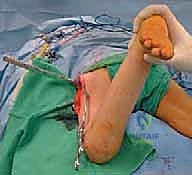

2. الفتح الجراحي والوصول للعظم

يتم عمل شق جراحي دقيق في الجزء الجانبي العلوي من الفخذ (المنطقة القريبة من الورك). يتم إبعاد العضلات برفق شديد للحفاظ على الأنسجة الرخوة والتروية الدموية للعظم، للوصول إلى منطقة "ما بين المدورين" (Intertrochanteric region).

3. إدخال السلك الدليلي (Guide Wire)

تحت توجيه الأشعة السينية المباشرة داخل غرفة العمليات (C-arm)، يقوم الدكتور هطيف بإدخال سلك دليلي في عنق ورأس عظم الفخذ بالزاوية الصحيحة والمحسوبة بدقة.

4. القطع العظمي (The Osteotomy)

باستخدام منشار جراحي دقيق جداً وعالي السرعة، يتم إجراء قطع عرضي في عظم الفخذ في المنطقة المحددة. هذه الخطوة تفصل الجزء العلوي (الرأس والعنق) عن الجزء السفلي (جسم العظم).

5. التدوير (Derotation)

هنا تكمن مهارة الجراح؛ يتم تدوير الجزء السفلي من عظم الفخذ (الساق بأكملها) إلى الخارج بالدرجة المطلوبة تماماً (عادة بين 20 إلى 30 درجة) لتصحيح الانحراف الأمامي المفرط وإعادة القدم إلى وضعية الاستقامة الطبيعية.

6. التثبيت الداخلي القوي (Internal Fixation)

لضمان التحام العظم في وضعه الجديد، يستخدم الدكتور هطيف نظام تثبيت عالمي يتمثل في صفيحة الشفرة الزاوية (AO 90-degree Blade Plate) أو مسامير وصفيحة مخصصة للأطفال. يتم إدخال الشفرة في عنق الفخذ، وتثبيت الصفيحة على جسم العظم باستخدام براغي معدنية قوية.

7. الإغلاق والتعافي

يتم التأكد من الاستقامة النهائية ومجال الحركة الميكانيكي للمفصل، ثم تُغلق الأنسجة والجلد بخياطة تجميلية دقيقة لتقليل الندبات.